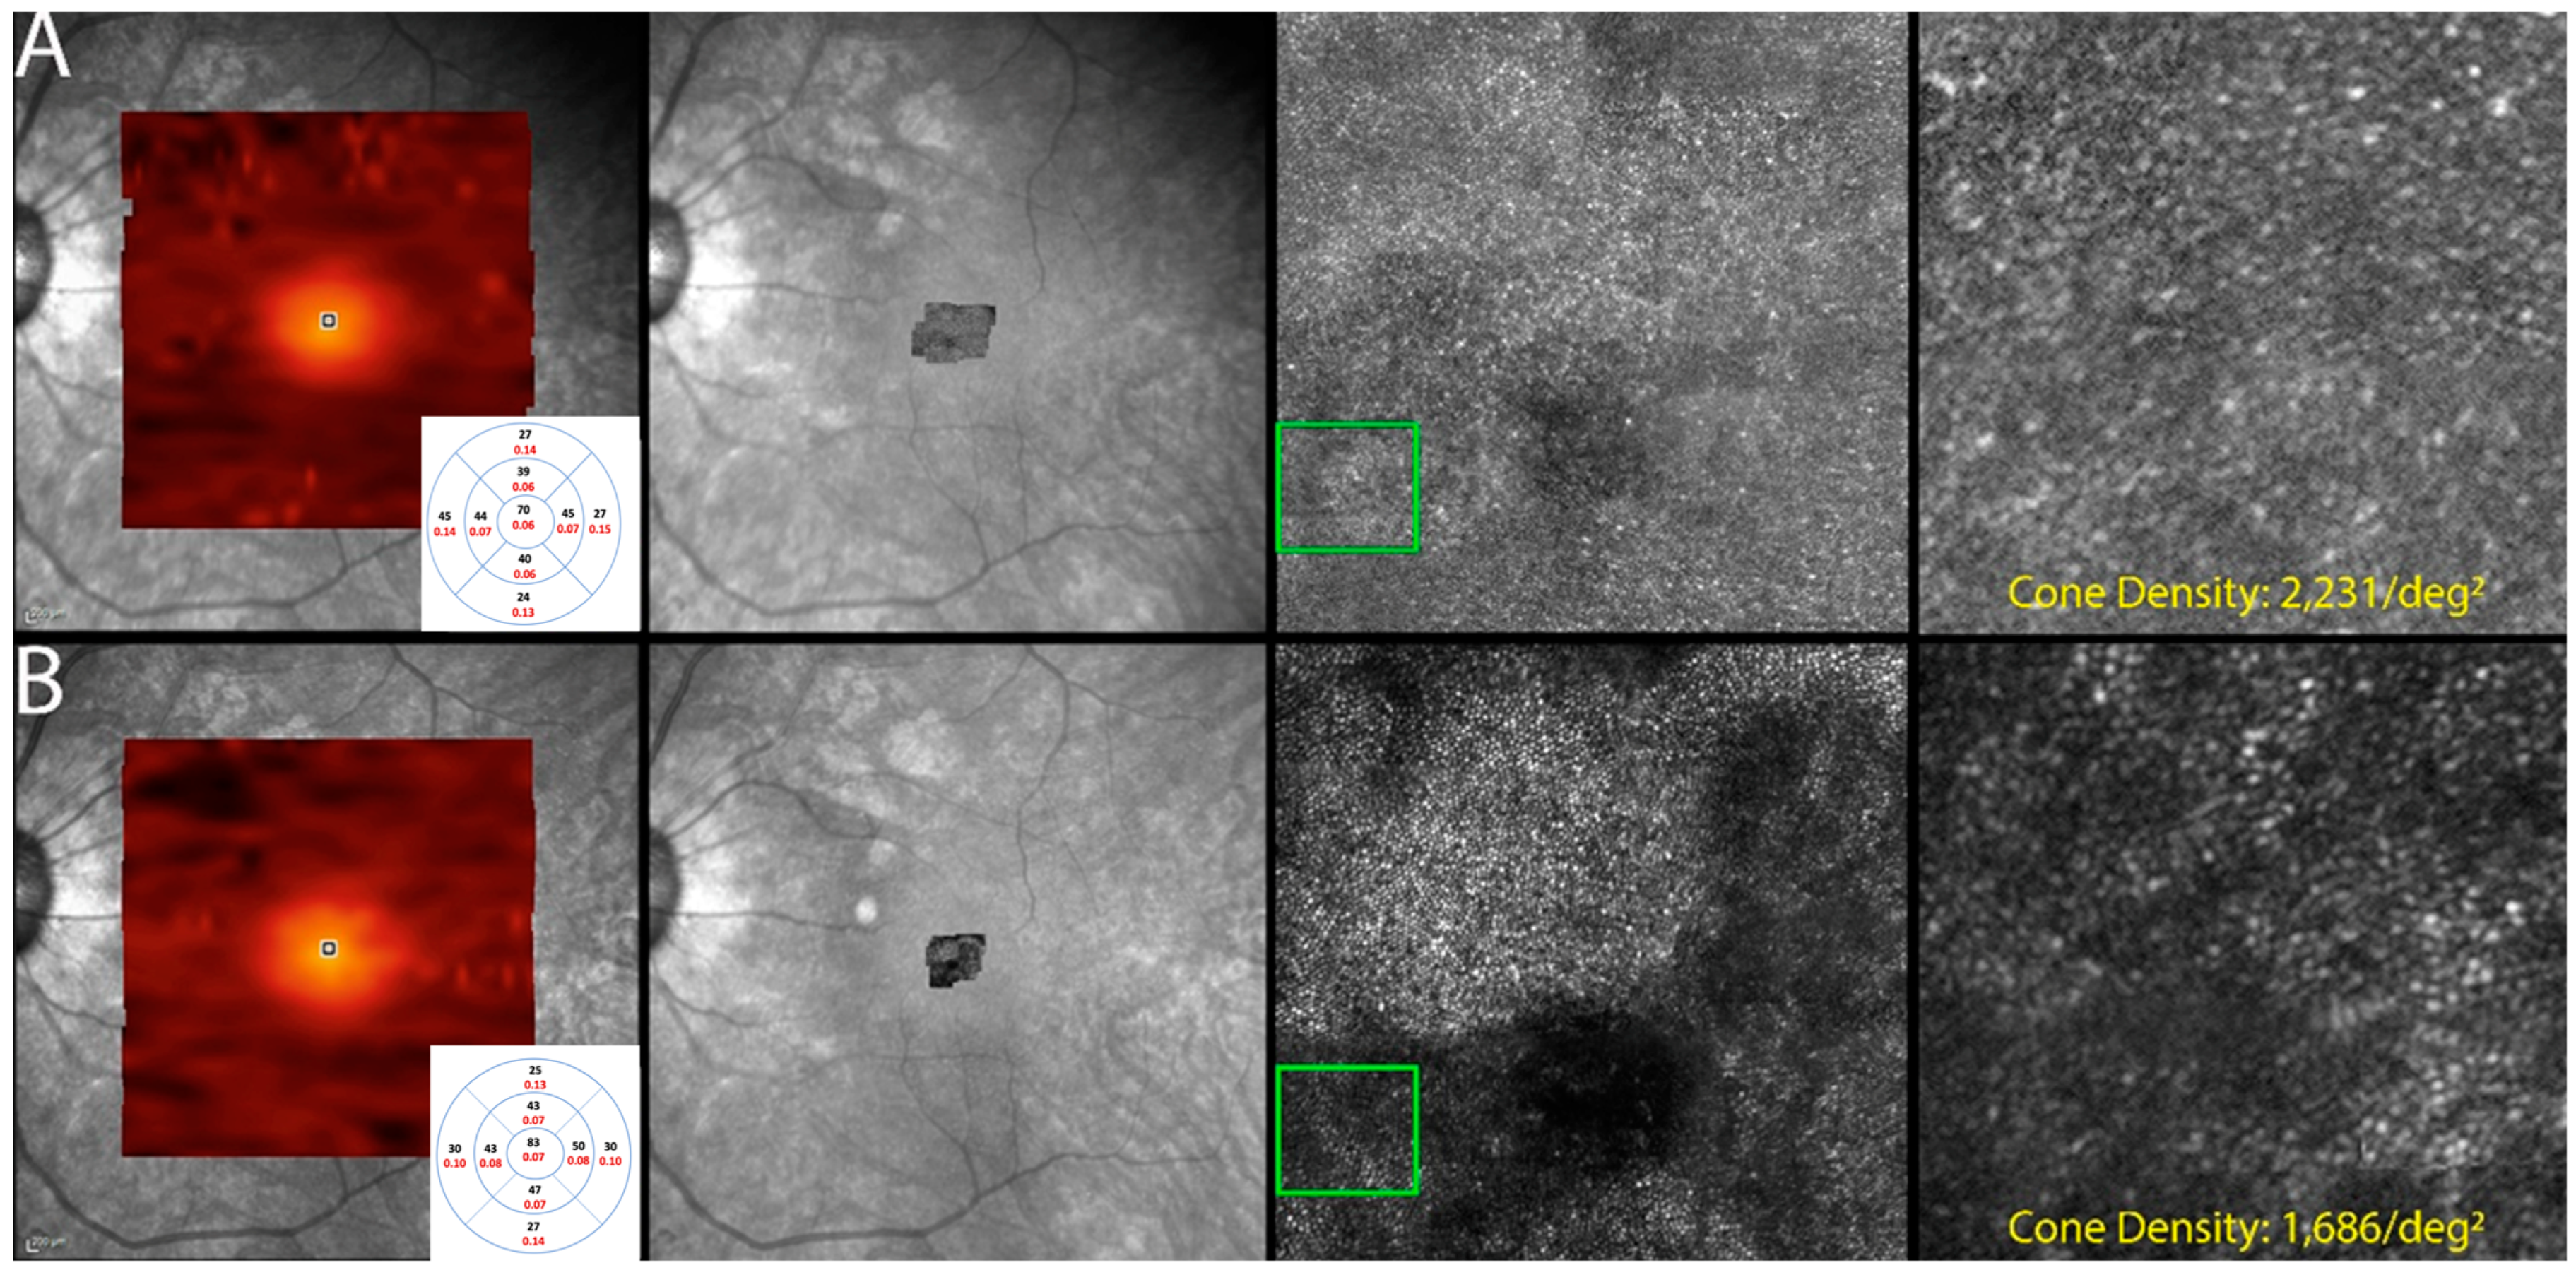

3.6. Adaptive Optics Scanning Laser Ophthalmoscopy

The use of AOSLO for cone quantification was attempted in six (75%) patients. Images suitable for cone quantification were obtained from ten eyes (83.3%) at the initial and follow-up visits. Quantification from the other eyes could not be established due to the low quality of the acquired images. Results are illustrated in Table 2.

Cone density was found to be decreased in all ten eyes that underwent imaging. Eyes with grossly visible changes in the photoreceptor mosaic image were in coherence with the deteriorating status of the macula, which was depicted by imaging modalities such as SD-OCT, showing EZ loss and also with subjective worsening (Figure 7).

Figure 7.

Optics scanning laser ophthalmoscopy (AOSLO) and detectable OCT changes in non-paraneoplastic autoimmune retinopathy (npAIR); images are from patient 2. This figure illustrates follow-up changes in the left eye of an npAIR patient (patient 2). Row (A) shows imaging performed at baseline, and row (B) shows follow-up imaging conducted at month 15. En face OCT showed a segmented outer retina with sparing of the central island and generally reduced outer retina thickness indices in the follow-up visit. The use of AOSLO enables visualization of the cone-photoreceptor mosaic. Semi-automated cone quantification of the preselected area in this cone-photoreceptor mosaic showed a decrease in cone density, which corresponds with retinal OCT findings.

AOSLO is a novel imaging technique that captures high-resolution images, allowing for the visualization of retinal microstructures directly. Our study is one of the few that has explored whether AOSLO can be used as a diagnostic/trend-analyzing tool in npAIR. Analysis of the cone-photoreceptor mosaic in standard size approximately 1 degree from the fovea in cases of npAIR revealed abnormal cone–photoreceptor morphology and decreased density on quantification. The data are similar to previous findings of another study that had imaged AIR patients using a commercially available AOSLO device [44]. In a case report, Williams et al. demonstrated a high correlation and accuracy between in vivo AOSLO results and the retina histology specimen finding of a CAR patient when the density of cone cells was evaluated [45].

Our study suggests that AOSLO has the potential to monitor disease progression in severe npAIR patients, as it enables quantification of retinal structures such as photoreceptors. Our study also demonstrates that cone density decreased as npAIR progressed. However, as our study population is small, further studies with larger sample sizes and more extended follow-up periods should be explored to validate our findings and explore what AOSLO may have in monitoring patients with npAIR.